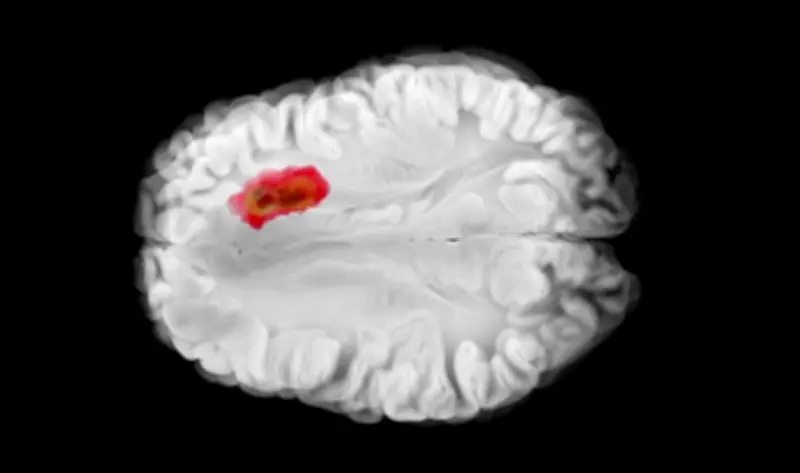

في تطور علمي مثير، كشفت دراسة حديثة نُشرت في مجلة طبية مرموقة عن دور حاسم لفيتامين معين في تعزيز جهاز المناعة البشرية لمحاربة أحد أخطر أنواع سرطان الدماغ، المعروف باسم الورم الدبقي. هذا الاكتشاف قد يفتح آفاقاً جديدة في تطوير علاجات أكثر فعالية لهذا المرض الخبيث.

أجرى فريق من الباحثين في جامعة كبرى دراسة شاملة على مجموعة من المرضى المصابين بسرطان الدماغ، حيث ركزوا على تحليل تأثيرات فيتامين د على جهاز المناعة. وجدت الدراسة أن هذا الفيتامين يعمل على:

• تحفيز الخلايا المناعية لمهاجمة الخلايا السرطانية في الدماغ.

• تقليل نمو الأورام من خلال تعزيز الاستجابات الدفاعية الطبيعية للجسم.

• تحسين فعالية العلاجات الحالية مثل العلاج الكيميائي والعلاج الإشعاعي.

وأشار الباحثون إلى أن نقص هذا الفيتامين في الجسم قد يضعف القدرة على مكافحة السرطان، مما يسلط الضوء على أهمية التغذية السليمة في الوقاية والعلاج.